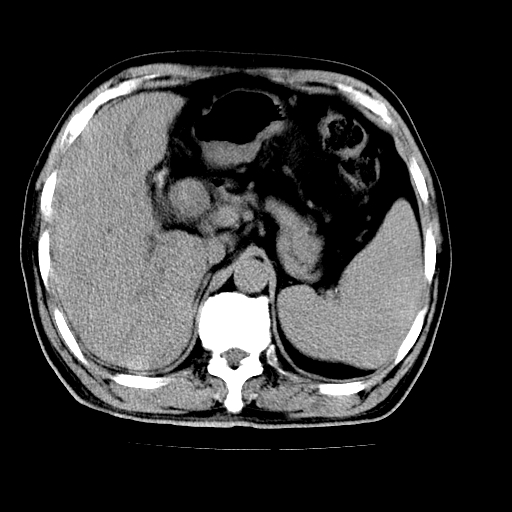

男,66岁,上腹部不适、黄染一周。彩超示:肝左叶占位,肝内胆管扩张,胆总管扩张,胆总管占位?

象胆管细胞癌,但又没有看见明显强化结节,陶瓷胆囊,十二指肠及胆总管显示不清晰,难下定论。

肝左叶不规则软组织肿块影,边缘不规整邻近肝实质受累分界不清;肝内胆管(左叶)明显扩张成“软藤状”,诊断:肝左叶胆管细胞癌。

左叶胆管细胞癌累及胆总管,门脉左支受侵,慢性胆囊炎胆结石,左肾小囊肿

支持 1)肝左叶胆管细胞癌伴胆总管及门脉左支受侵。2)胆囊钙乳症。